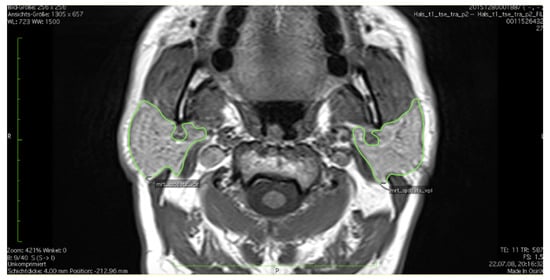

2.2. Standard Operating Procedure